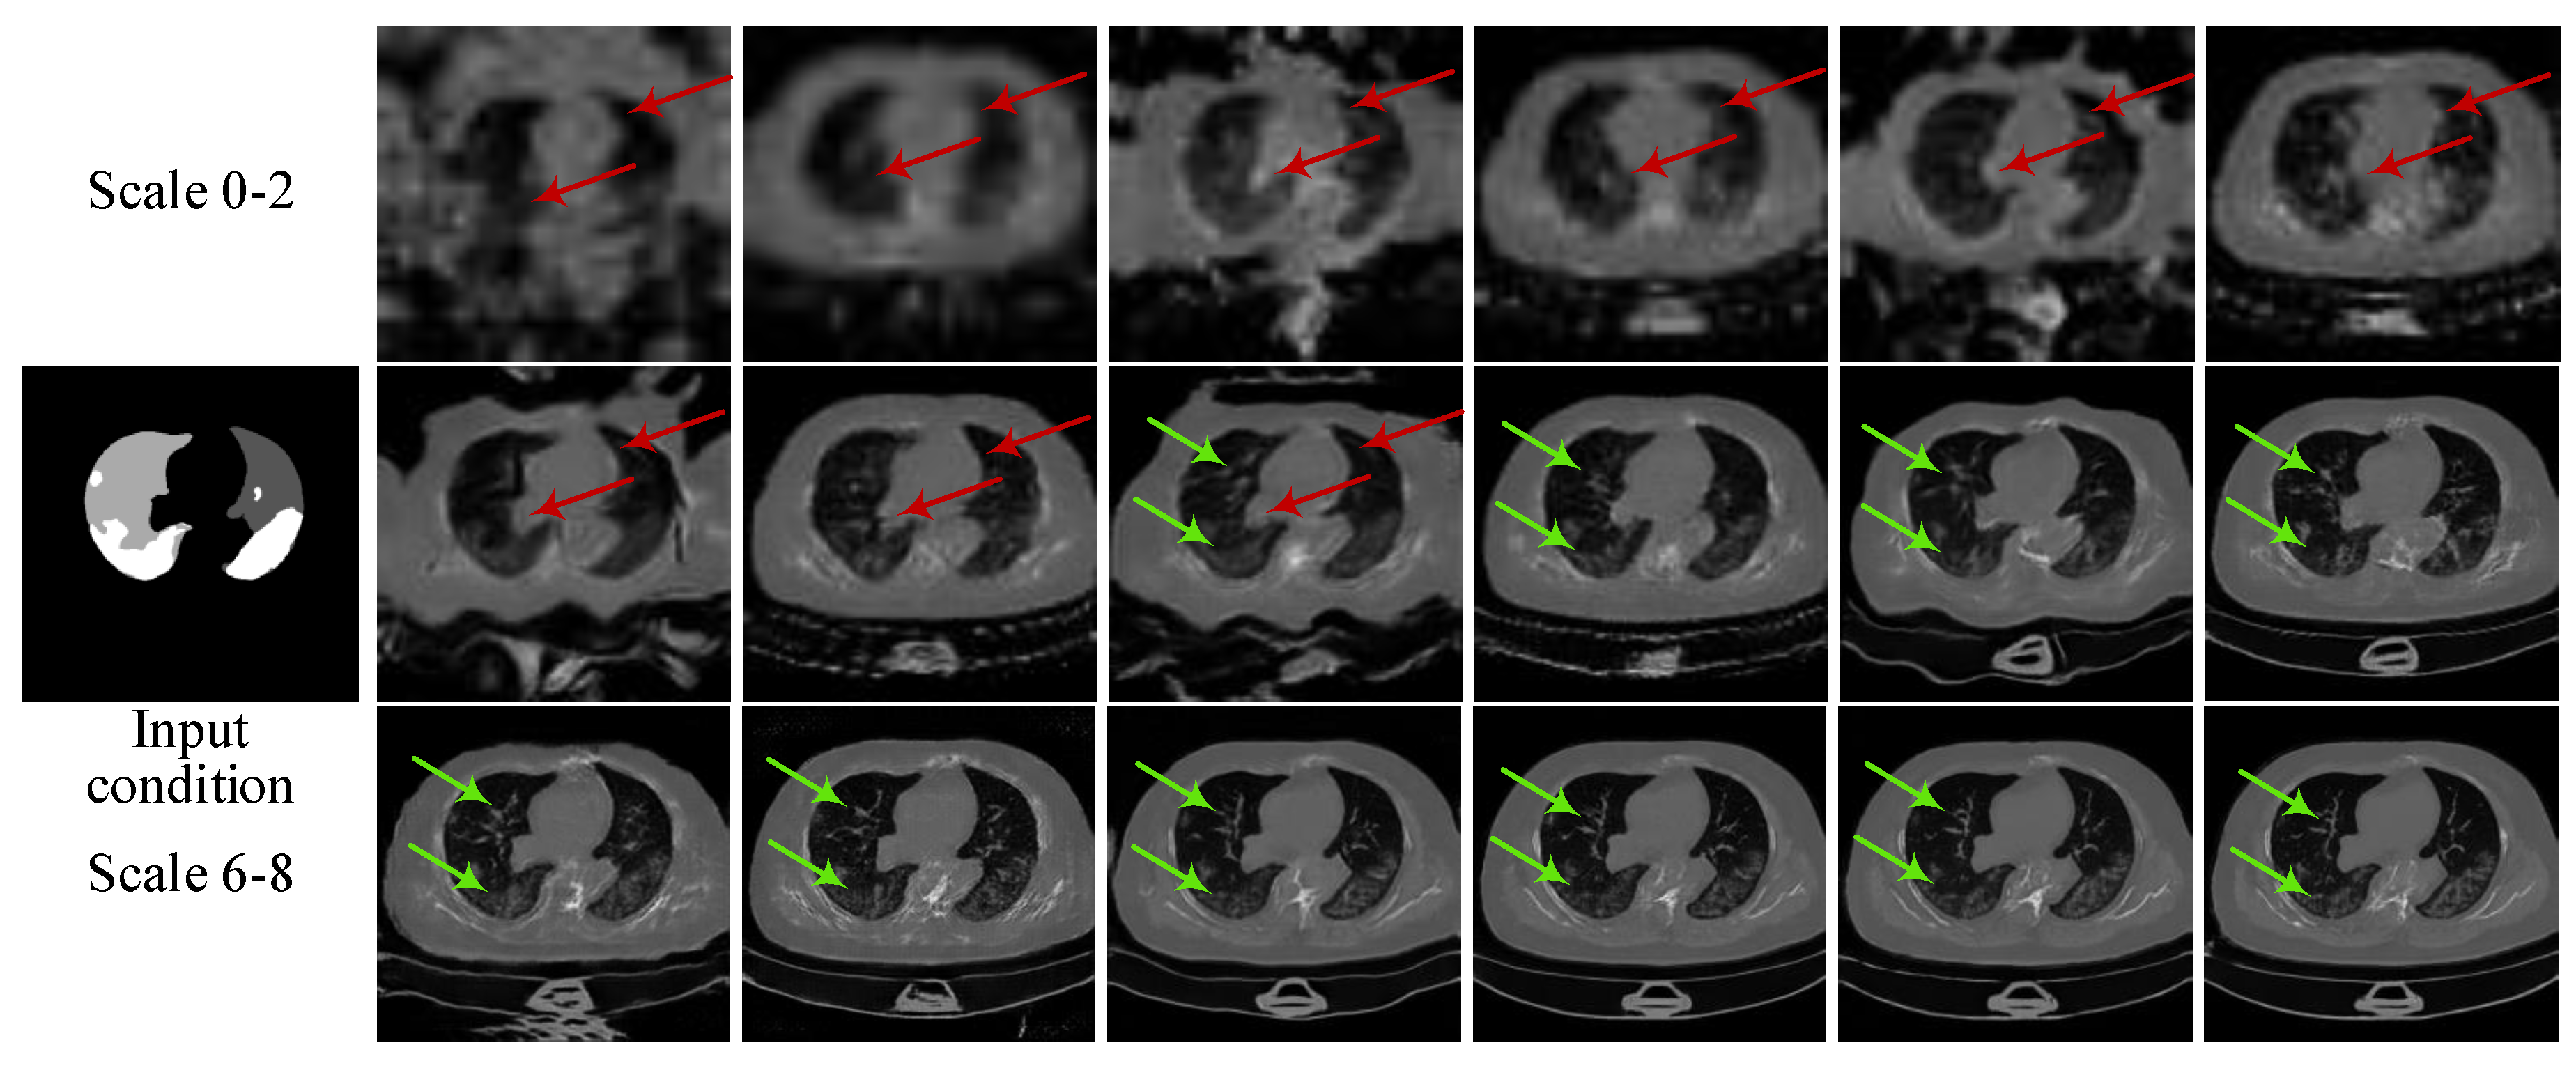

2.1.1. Multi-Scale Architecture with a Pyramid of Two-Stage GANs

3.1.2. Ablation Experiments